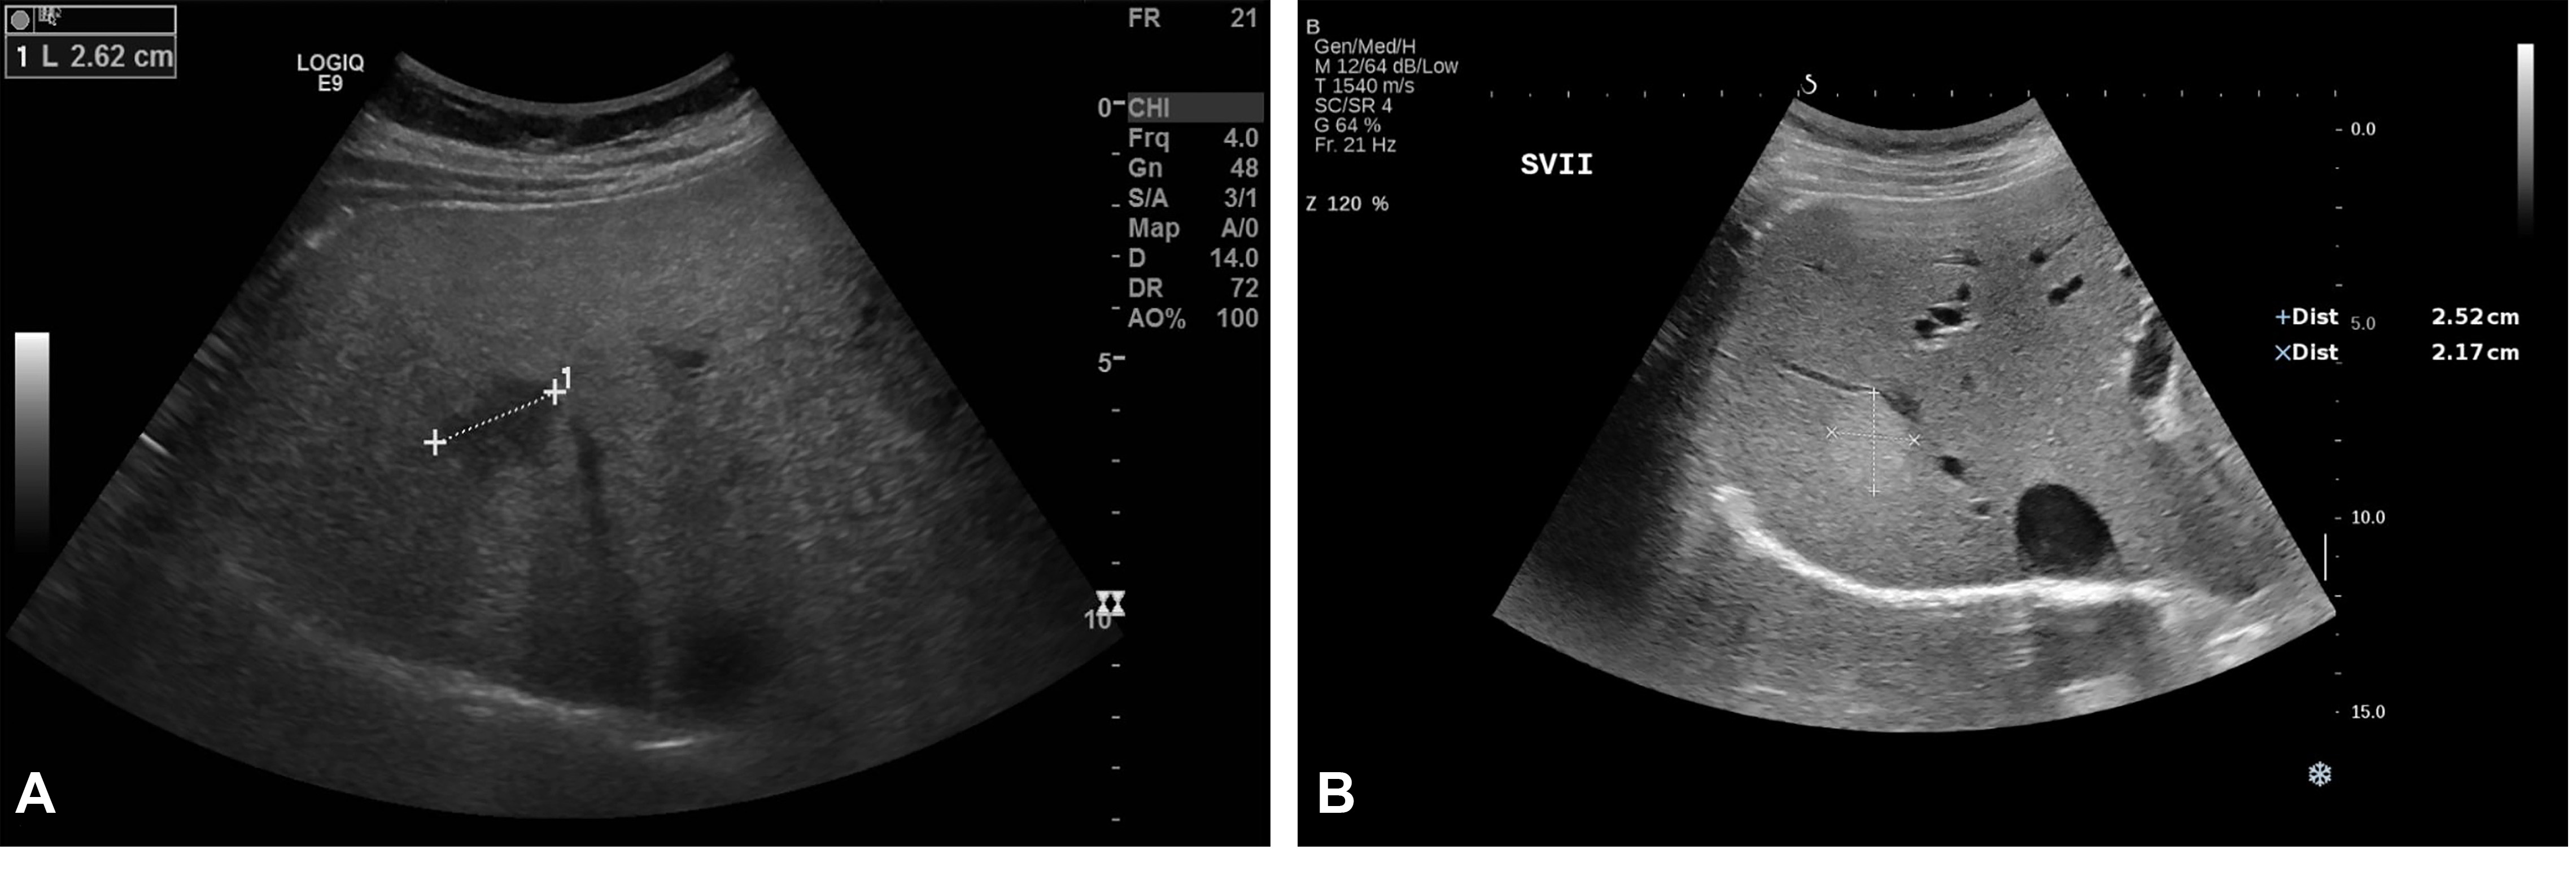

Figure 2. Conventional US revealed a hypoechoic lesion in segment VII in a 71-year-old man with non-alcoholic liver cirrhosis. Ultrasound attenuation can be observed in deep segments. The lesion was a hepatocellular carcinoma.